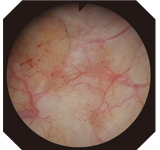

Narrow Band Imaging (NBI) is the World's Only Patented Endoscopic Light Technology for enhancing the visualization of vascular structures without the use of dyes, drugs, or contrast agents. NBI, which is strongly absorbed by hemoglobin and penetrates only the surface of tissues, is ideal for highlighting areas of increased vascularity. As a result, under NBI, capillaries on the mucosal surface are displayed in brown on the monitor, and veins in the submucosa are displayed in cyan. NBI is simple to use. With no dyes or drugs, no time limit of effectiveness, and no added cost, NBI is an easy addition to your standard procedure work flow.

Conventional image